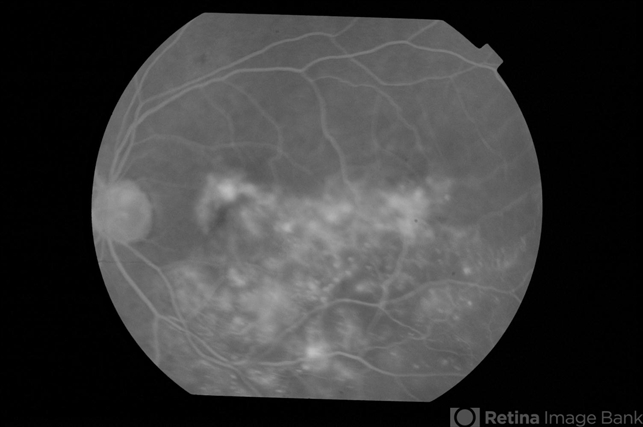

- Adult Coats Disease

- Left fundus of a 61-year-old non diabetic, non hypertensive lady complaining of vision deterioration for 1 year showed massive hard exudates at the macula. Fluorescein angiography revealed microvascular abnormalities over the posterior pole and temporal midperiphery and extensive capillary non-perfusion over the temporal retinal quadrants. OCT revealed macular edema. Fellow eye fundus and angiogram were normal.